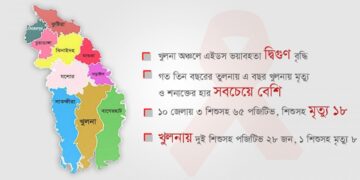

হার্টবিট ডেস্ক বেসরকারি একটি সংস্থায় অ্যান্টি রেক্ট্রোভাইরাল থেরাপি নিতে আসেন খুলনা মহানগরীর বাসিন্দা আবু হানিফ (ছদ্মনাম)। তার চার বছরের...